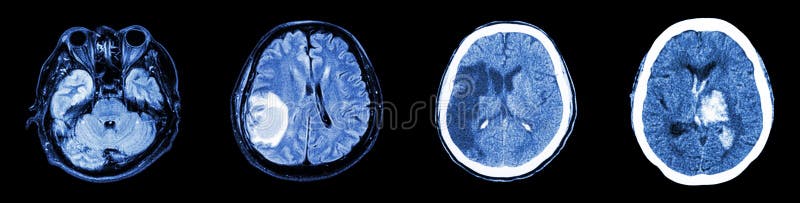

Neuroimaging Avanzato Dell Ictus

Basi Chimico Fisiche Dell Imaging Tc Ed Rmn Delle Emorragie Intracraniche Neuro E Non Solo Fermononrespiri

Chronic Subdural Hematoma Importance Of Dural Membranes Radiology Case Radiopaedia Org

Ictus Ischemico Malattie Neurologiche Manuali Msd Edizione Professionisti

La Dignostica Per Immagini Nella